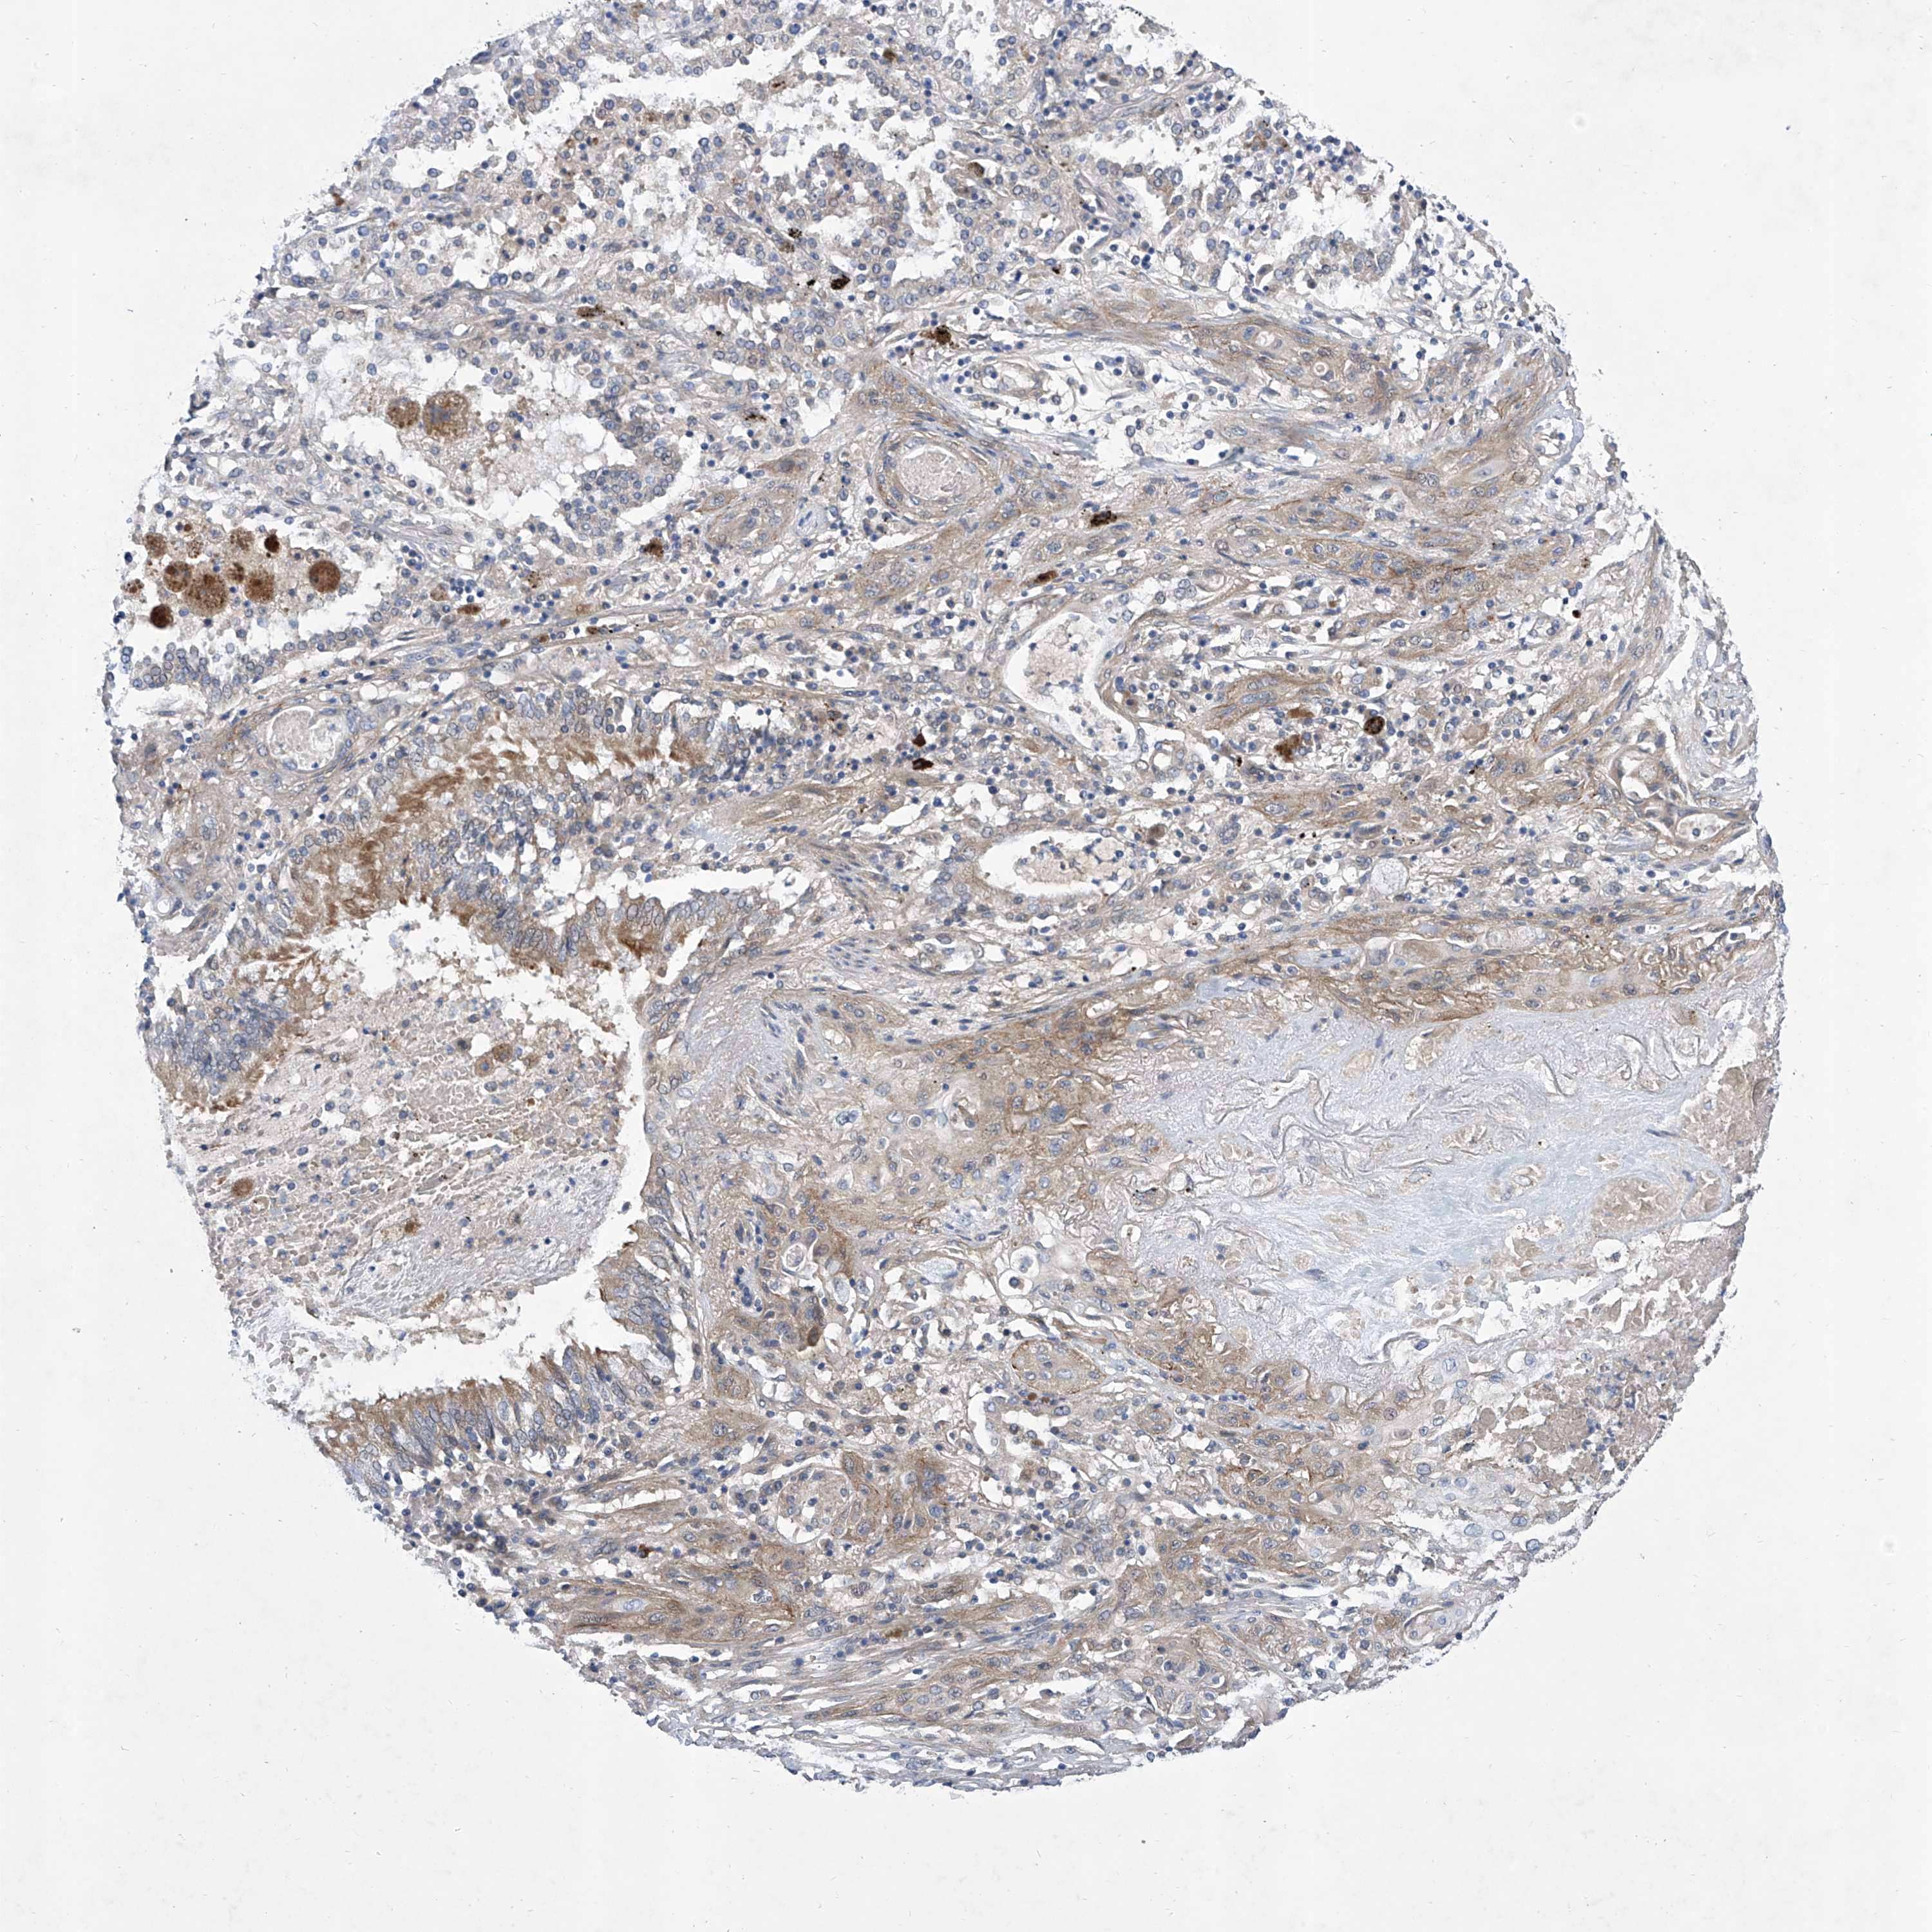

CANCER LUNG CANCER Show tissue menu

LUAD TCGA LUAD VALIDATION LUSC TCGA LUSC VALIDATION PROTEIN LUAD CPTAC PROTEIN LUSC CPTAC PROTEIN EXPRESSION